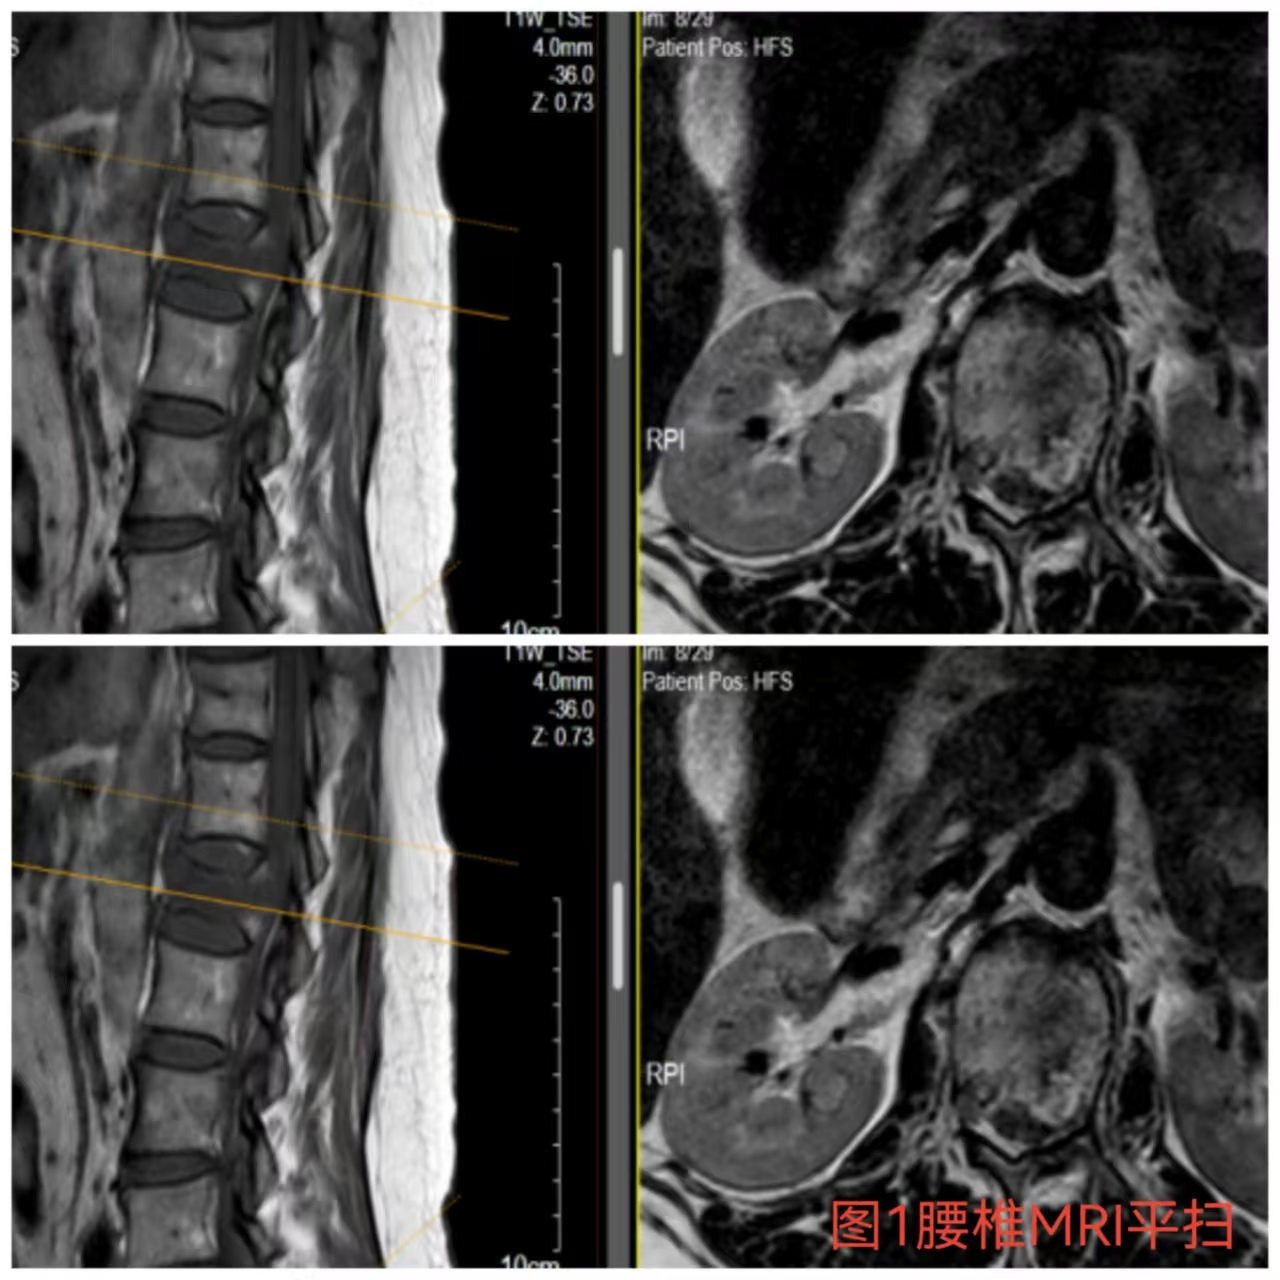

入院时患者躺在床上不可转动,,,,眼神中透漏着深深的无助,,,,关于她来说这种伤情无疑是极重的,,,,尤其是腹股沟以下感受消逝、双下肢肌力0级,,,,这意味着其下肢无法活动及站立,,,,似乎被运气按下了暂停键;;与病人及眷属充分相同病情后,,,,第一时间给予对症治疗,,,,监测患者生命体征,,,,行腰椎核磁检查(图1)提醒:腰1椎体爆裂性骨折,,,,椎体后缘塌陷致骨性椎管狭窄,,,,榨取脊髓神经,,,,连系患者病情及辅助检查可诊断为:“L1椎体爆裂性骨折伴双下肢截瘫”。。。。